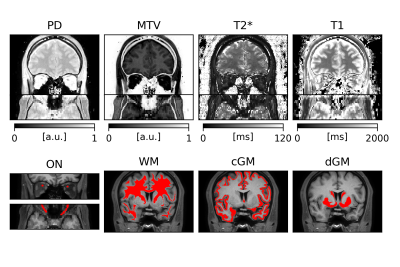

An overview of PD, MTV, T2* and T1 quantitative maps, together with ON, WM, cGM and dGM masks, is displayed in Figure 1. Distributions of regional values are shown in Figure 2. Laterality tests are reported in Figure 3, with significant differences observed in PD ($$$p=0.003$$$), MTV ($$$p=0.003$$$) and T1 ($$$p=0.031$$$) between left and right ON; the same significant trends were observed between left-right fronto-temporal WM ($$$p=0.026$$$, $$$p=0.026$$$, $$$p=0.025$$$, respectively). CV scores are reported in Table 1, with CVs below 10% observed for all metrics and all tissues except for MTV, where CV of up to 28% was calculated.

Figure 1. Examples of quantitative maps and regional masks for a single subject. Top row: PD, MTV, T2* and T1 quantitative maps coronal and axial slices. Bottom row: ON (coronal and axial slices), WM, cGM and dGM masks. The ON masks have been dilated for better visibility.